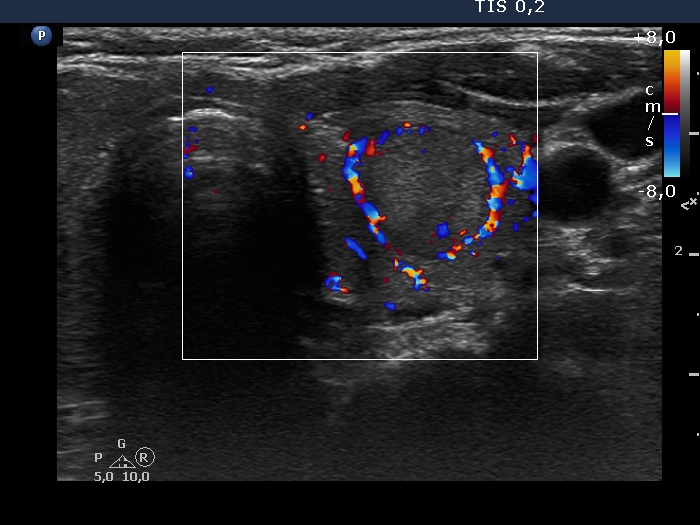

Discrete lesion or nodule in Hashimoto's thyroiditis - case 18 (99) (ultrasonographic picture 7)

Left lobe, transverse scan, color Doppler mode. The lesion has an almost complete perinodular blood flow.